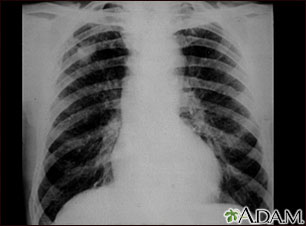

This chest x-ray shows coal workers pneumoconiosis - stage II. There are diffuse, small (2 to 4 mm each), light areas throughout both lungs. In the right upper lung (seen on the left side of the picture), there is a light area (measuring approximately 2 cm by 4 cm) with poorly defined borders, representing coalescence (merging together) of previously distinct light areas. Diseases which may explain these x-ray findings include simple coal workers pneumoconiosis (CWP) - stage II, silico-tuberculosis, disseminated tuberculosis, metastatic lung cancer, and other diffuse infiltrative pulmonary diseases.